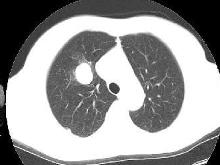

5、CT检查 可以较清楚地显示病变的形态,还可确认异常动脉的存在。典型表现为:正常肺支气管动脉和静脉束远离或围绕在隔离肺叶外周,偶见钙化。如与支气管树交通造成感染,其表现为含气囊肿,有或无液平,周围可见炎性浸润,也可呈囊肿样表现,可有气液平。但诊断阳性率并不高。